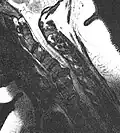

Herniated disc at C6–C7 level

Cervical disc herniations occur in the neck, most often between the fifth and sixth (C5–6) and the sixth and seventh (C6–7) cervical vertebral bodies. There is an increased susceptibility amongst older (60+) patients to herniations higher in the neck, especially at C3–4.[23] Symptoms of cervical herniations may be felt in the back of the skull, the neck, shoulder girdle, scapula, arm, and hand.[24] The nerves of the cervical plexus and brachial plexus can be affected.[25]